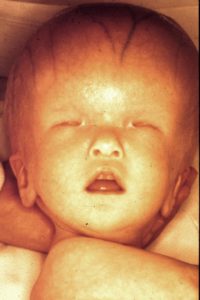

Anophthalmia and Dysmorphic Syndrome

Note what signs you see.

I (W. Wertelecki, M.D.) see a relatively large head and no evidence of ocular globes.

PERSPECTIVE: Clinically (without an autopsy) it is not possible to distinguish agenesis from aplasia of ocular globes (lack of genes or lack of expression). In any case, it is fundamental to remember that the eyes derive from the cerebral frontal lobes. Another perspective is whether there are extra-cephalic concurrent malformations (as in this case).

Please, see four additional images of this patient.